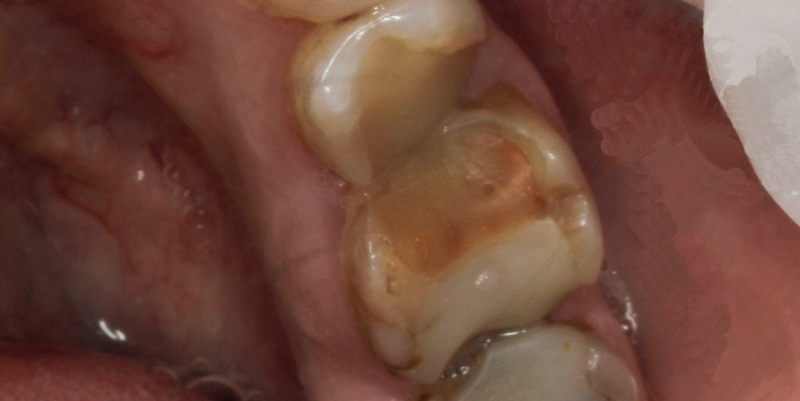

До и после лечения

Пациент обратился в «Стоматологию Комфорта» с жалобами на разрушенное состояние зубов, невозможность полноценно пережевывать пищу. В ходе диагностики врач Шандро Евгения Богдановна поставила диагноз: кариес дентина зубов 3.6, 3.7. Врач принял решение о лечении кариеса с заменой непригодных композитных реставраций на керамические накладки Оверлей.